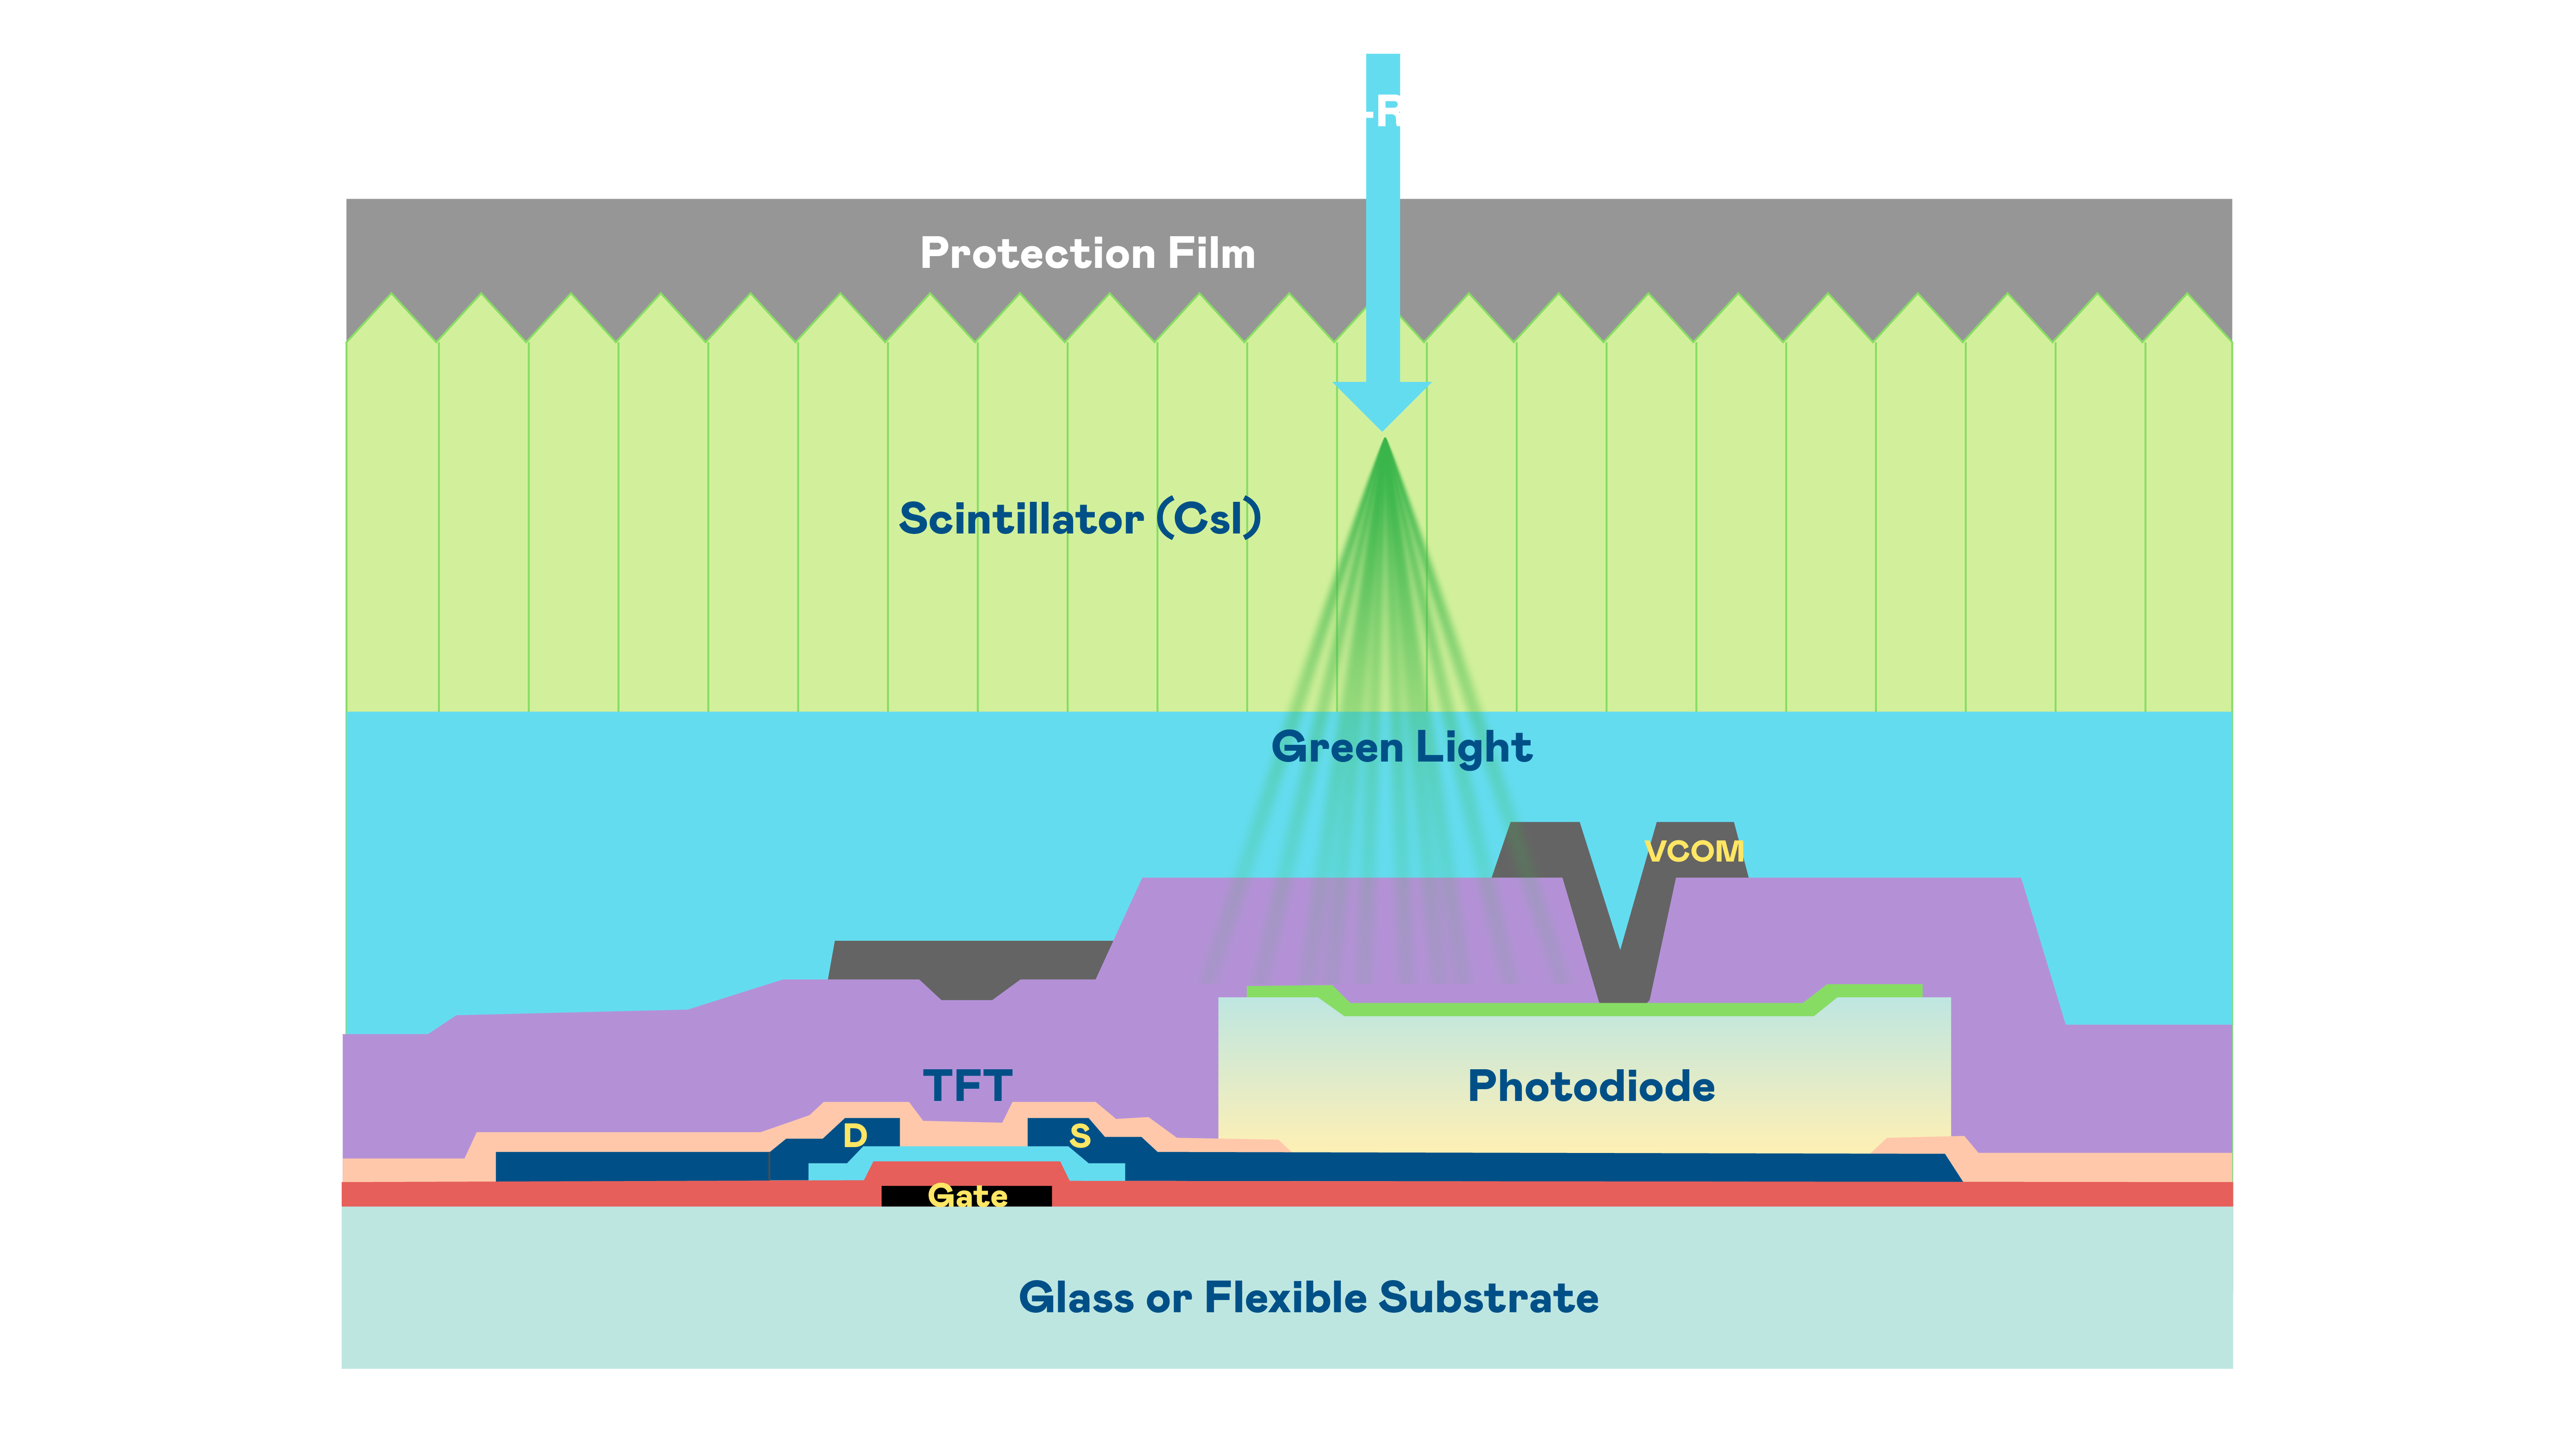

AUO's X-ray image sensor array uses TFT as readout switches for each pixel, along with photodiodes as the photoelectric conversion elements to detect X-ray image signals.

The product technology categories include glass and flexible imaging sensor arrays, a-Si and IGZO TFT technology platforms, as well as X-ray sensor module products that combine scintillator layers with readout chip-on-film (COF) technology.